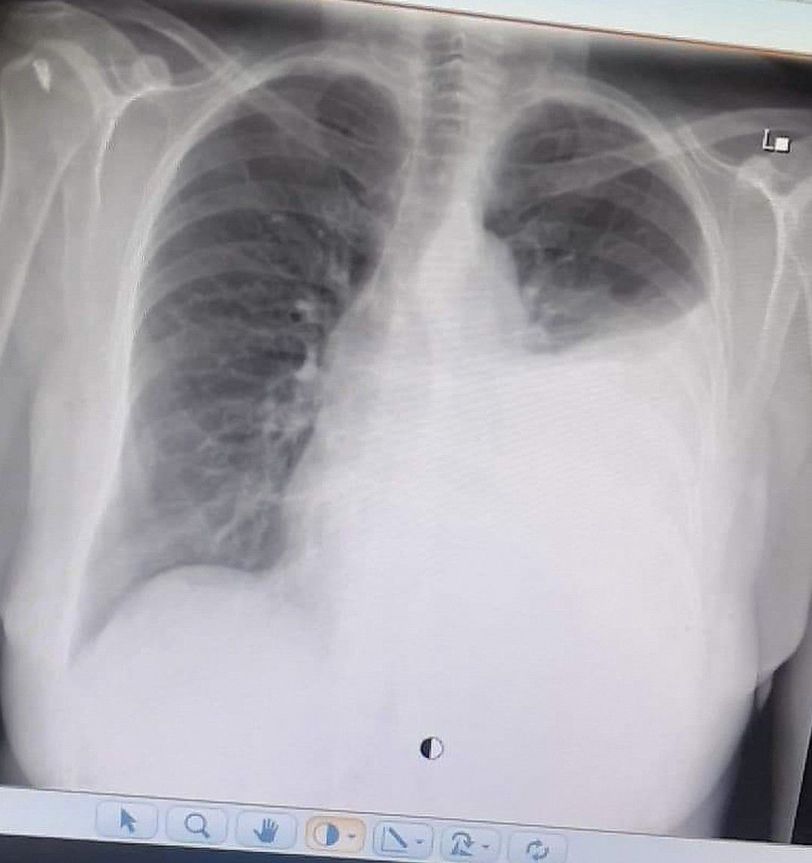

Pulmonary edema

It’s seems to be effusion